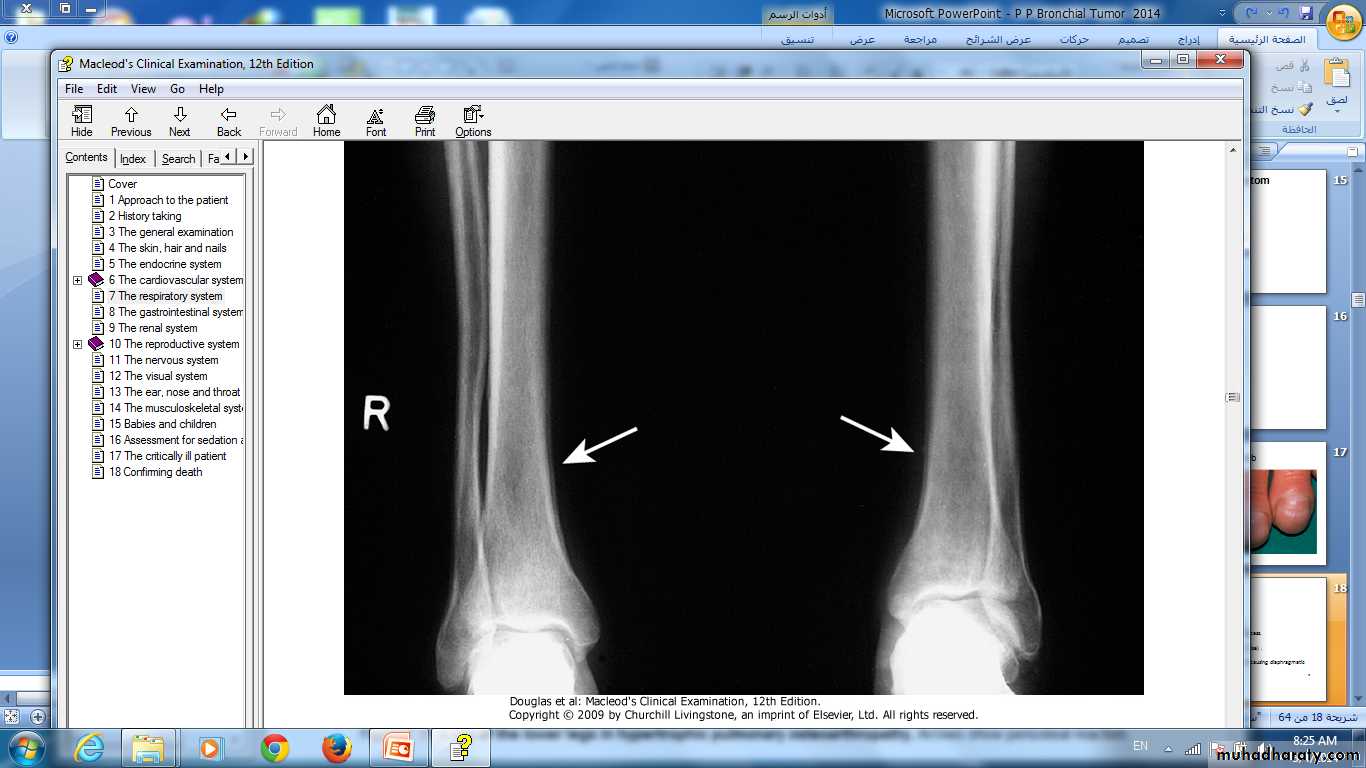

X-ray of the lower legs in hypertrophic pulmonary osteoarthropathy. Arrows show periosteal reaction

Hypertrophic pulmonary osteoarthropathyNephrotic syndrome